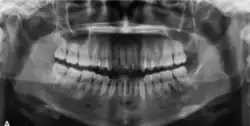

Radiographically, COF appears as a well-defined unilocular lesion. In large mandibular cases, it may cause downward bowing of the inferior border.[13] Tooth displacement is common, while root resorption is less frequently observed.[13] If untreated, the lesion can grow substantially. Surgically, COF is usually well-demarcated from the surrounding bone and often easily enucleated. Some lesions may also exhibit a distinct capsule.[11]

In its early stages, central ossifying fibroma (COF) appears as a small, well-defined radiolucent lesion due to its fibrous tissue content. Differential diagnoses at this stage include periapical pathology, central giant cell granuloma, and ameloblastoma.[22][23] As the lesion matures, it exhibits a mixed radiolucent-radiopaque appearance due to progressive calcification.[22] At this stage, it should be differentiated from other mixed jaw lesions such as fibrous dysplasia, calcifying epithelial odontogenic tumour, adenomatoid odontogenic tumour, and condensing osteitis.[22] In its mature form, COF may appear predominantly radiopaque, resembling lesions like odontomas, osteoblastomas, or osteosarcomas radiographically.

COF typically presents with well-defined, smooth, and often corticated borders. As a central lesion, it originates within the medullary bone and expands concentrically in all directions.[24] With growth, it may cause tooth displacement, root resorption, inferior displacement of the mandibular canal, and loss or alteration of the lamina dura of adjacent teeth.[25]

In conclusion, COF most commonly occurs in the mandible and expands from a central epicenter. Radiographically, it presents as a well-defined mixed-density lesion,[26] and Cone Beam CT (CBCT) plays a crucial role in its accurate diagnosis and assessment.

Central Ossifying Fibroma (COF) typically presents as a painless swelling in the posterior mandible, though maxillary involvement can also occur.[31] Larger lesions may lead to facial asymmetry and displacement of adjacent teeth.[32] Radiographically, COF appears as a well-circumscribed, mixed radiolucent–radiopaque lesion with a characteristic sclerotic border, and the degree of radiopacity reflects the stage of mineralization.[33] Cone-beam computed tomography (CBCT) offers detailed evaluation of cortical expansion, root displacement, and internal architecture.[34]